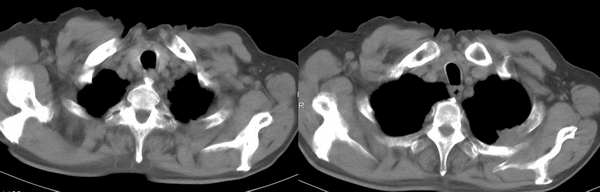

病变两次对照有明显进展,临近肋骨破坏,胸膜增厚,无胸水;首先考虑周围型肺ca。

和2月份片比较病灶明显增大,且有向胸壁侵犯的倾向,应该首先考虑周围型肺癌。

2左上胸壁疼痛,不适.影像表现胸膜下脂肪间隙消失,考虑胸膜有侵犯。